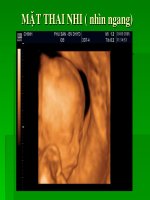

Mặt cắt dọc giữa chuẩn

Tư thế ngửa

Maởt caột doùc giửừa

Chỉ thấy đầu và ngực